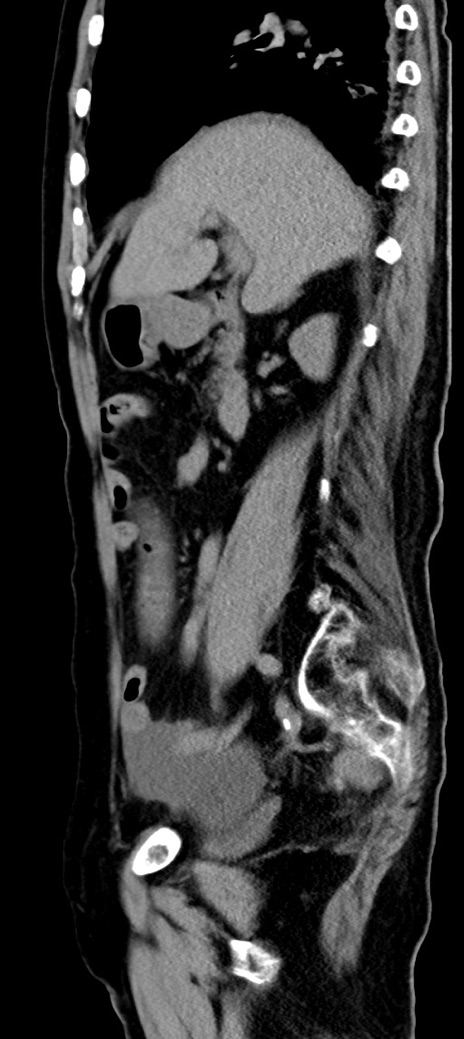

症例40(矢状断像)他院1日前

【症例】90歳代女性

【主訴】腹痛・嘔吐

【現病歴】 食欲低下、嘔吐があり昨日他院受診。肺炎と診断され入院となる。入院後より腹部全体に圧痛あり。胃管留置され経過みていたが、症状持続するため、

当院転院となる。

【既往歴】胸椎圧迫骨折、胆石症

【身体所見】腹部:中央に激痛あり、圧痛あり、反跳痛不明

【データ】WBC 17100、CRP 18.82